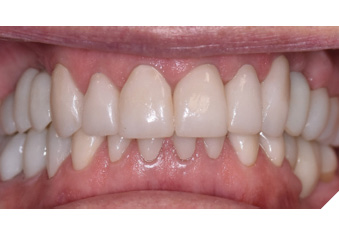

Articulated diagnostic casts showed very limited to no overjet and 90% of overbite. The wear pattern on the palatal aspect of her maxillary teeth appeared to be secondary to her tight occlusion since mandibular anterior teeth were in close contact with these surfaces with no “room” for protrusive movements. The diagnosis for this patient was: partial edentulism, failing existing restorations and attrition and abfraction secondary to parafunction. We discussed different options, including orthodontics in order to increase her overjet so we could have prosthetic space to restore her worn down teeth. We also discussed tooth replacement options. After a second consultation appointment which she attended with her husband, she decided that she did not want to replace her teeth with removable prosthetics. She also declined referral to an orthodontist. After discussion of multiple options of treatment to address all her chief complaints, her treatment consisted of a full mouth reconstruction with full coverage restorations in Zirconia for teeth 11-13,17,22-23,25-27,32-42, 44-47 and partial coverage restorations with lithium disilicate restoration for teeth 33,34 and 43. Replacement of teeth was achieved with a fixed partial denture to replace tooth 36 and a 3-unit implant supported bridge to replace teeth 24-26. In terms of occlusion, we created a more favorable occlusion with a proper anterior guidance, canine disclusion with more freedom for protrusive movements, which hopefully would decrease the parafunction, and alleviate some of her muscle pain. Before completing the case, the patient spent several weeks with provisional restorations which reflected the increase in vertical dimension of occlusion and the new occlusal scheme. During this trial phase, we assessed comfort, esthetics, function, decrease in pain and speech (Figs. 12-17).

Fig. 12

Fig. 13

Fig. 14

Fig. 15

Fig. 16

Fig. 17

During a 6 month follow up visit, the patient presented with reduced pain in her masticatory muscles and no sensitivity on her teeth. She was also pleased that her chewing function had improved and she loved her brighter smile. She used her night guard every night. She is in a 6-month recall protocol to ensure all restorations are in proper condition and that her occlusion continues to be ideal. We also monitor the health of the soft tissues and peri-implant health.